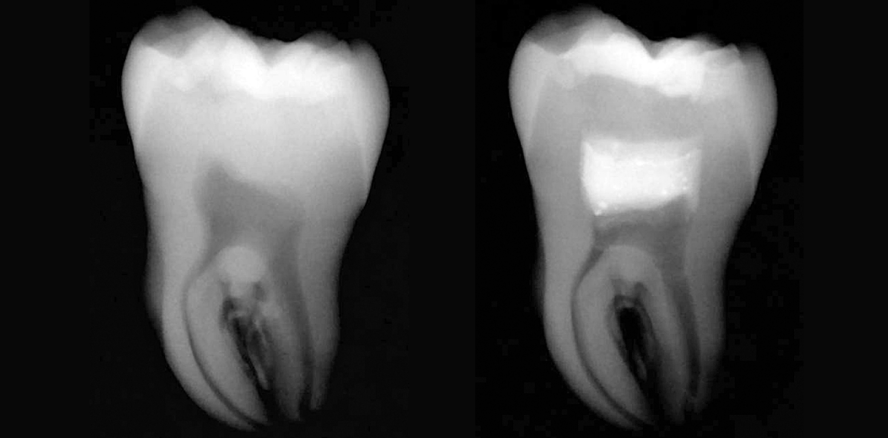

Die Abbildungen 8 bis 11 zeigen eine vitale Pulpatherapie mit MTA+ in Zahn 38 bei einem 60-jährigen männlichen Patienten. Der Zahn an sich war klinisch symptomlos und sensibel auf Kälte. Da der Ausschnitt der Bissflügelaufnahme schon ein hohes Pulpaeröffnungsrisiko zeigte, wurde mit dem Patienten zudem auch das Vorgehen bei einer Nerv-Eröffnung erörtert. Für den Patienten kam eine Wurzelkanalbehandlung an 38 nicht infrage, aber er war offen für eine Kompositrestauration mit MTA.

Nach Anlegen von Kofferdam und anfänglicher Entfernung der alten Füllung, löste diese sich komplett und eine wohl schon länger mit dem Mundraum verbundene Pulpa war sichtbar. Nach Behandlung des Kofferdams mit CHX 2 % folgten nun nachkommende Schritte:

Retrospektiv wäre mir in diesem Fall, aufgrund der lange dem Mundraum exponierten Pulpa, eine hohe Pulpotomie die sichere Option gewesen. Regelmäßige Nachkontrollen werden zeigen, ob der Zahn erhalten werden kann. Eine Literaturliste erhalten Sie auf Anfrage.